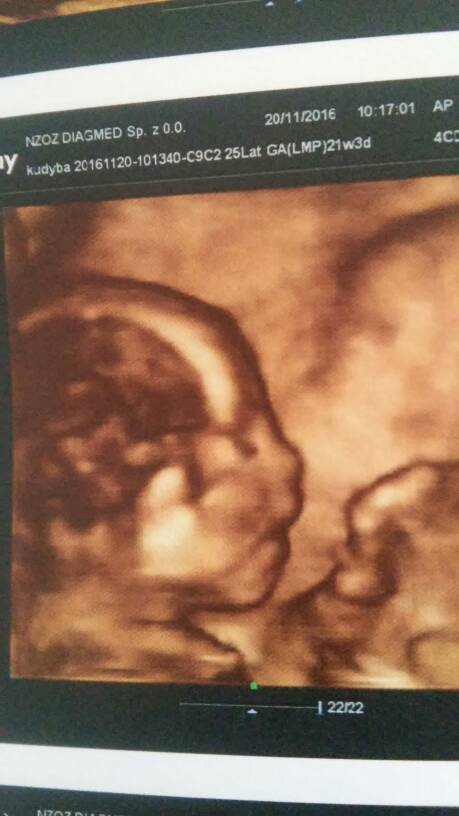

No to polowkowe za mna:) dziecie wszystko ma zdrowe i prawidlowe:) aktualnie tylkiem w dół sobie plywa. Wazy 433g i rozmiary i wszystko idealnie z om. Powiedzialam mu odrazu ze nie chce znac plci a on mowi ze podaje tylko jak ktos zapyta hehe no i dodal ze bedzie tak robil zebym sie nie kapnela. Tam jest tv przed oczami wiec lipilam na brzuch swoj[emoji23] jak mowil ze stopki pokazuje czy buzie,serduszko,mózg raczki to patrzylam a jak mowil ze pecherz czy cos w tym stylu to moj brzuch byl taaaak interesujący:)

W opisie mam ze lozysko z tyl....no to teraz nie wjen czy nie zmienil sb tej inf w tym jego szablonie czy jakims cudem przeskoczylo...musze mojego zapytac 1.12gdzie ono w koncu jest hehe[emoji23]